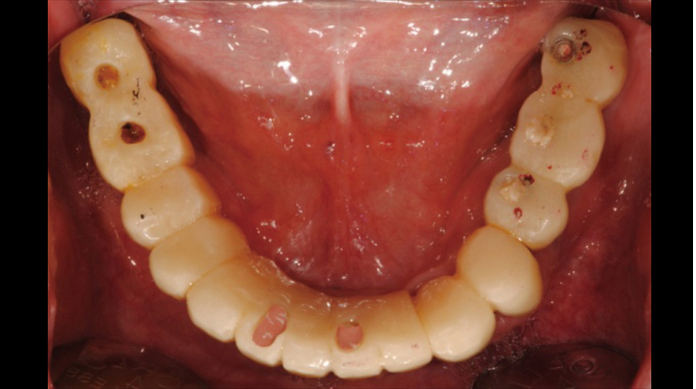

“AnyRidge ensures long-term biological stability

& functionality even in

full-mouth rehabilitation case. ”

Clinical case: Full-mouth implants for mandibular & maxilla - restored using mixed prostheses

- Courtesy of Dr. Hyun Jun Kim, Korea -